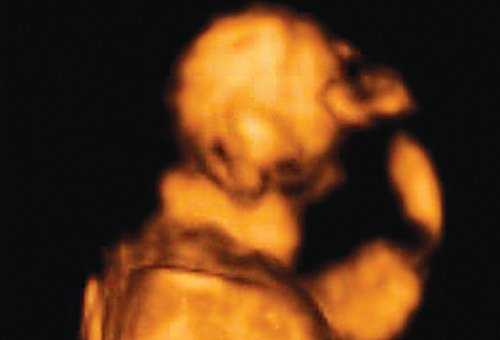

При эхографии в срок 13 недель 3 дня фетометрические параметры плода соответствовали гестационной норме, толщина воротникового пространства составила 1,5 мм; длина костей носа - по 2,5 мм. При трансвагинальном сканировании были обнаружены: затылочное энцефалоцеле размерами 7,4х3,5х3,7 мм (рис. 1), полидактилия кистей (рис. 2), увеличенные кистозно-измененные почки: правая - 28,5х21,3 мм; левая - 26,4х18,7 мм (рис. 3). Объем амниотической полости был нормальным для данного срока.

Синдром Меккеля. Диагностика и прогноз при синдроме Меккеля